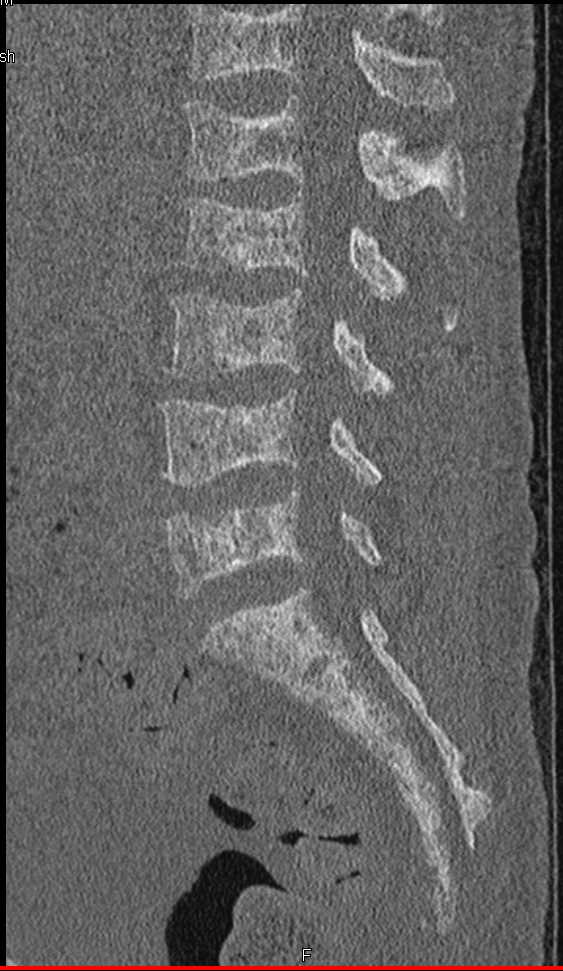

Diagnosis

Tibial Plateau Fracture